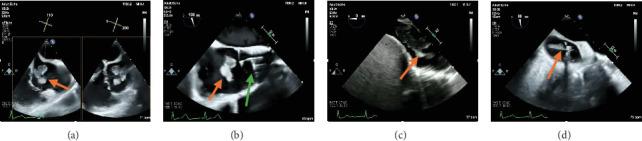

重复使用AngioVac清除延伸至肝静脉的巨大右心房血栓。

Repeat AngioVac Debulking of a Large Right Atrial Thrombus With Extension From the Hepatic Vein.

The AngioVac mechanical aspiration system has emerged in the literature as a viable treatment option for patients with intracardiac masses and thrombi and who are deemed high risk for cardiac surgery. Notably, it has been shown to be an effective treatment modality for the debulking of thrombi in the setting of malignancy. We present a case of repeat AngioVac debulking of a large right atrial thrombus with extension from the hepatic vein in the setting of advanced malignancy complicated by endocarditis.

摘要

血管内真空机械抽吸系统在文献中已成为心内肿块和血栓患者以及被认为心脏手术高风险患者的一种可行治疗选择。值得注意的是,它已被证明是在恶性肿瘤情况下清除血栓的有效治疗方式。我们报告一例在晚期恶性肿瘤合并心内膜炎的情况下,对从肝静脉延伸而来的巨大右心房血栓进行重复血管内真空清除术的病例。